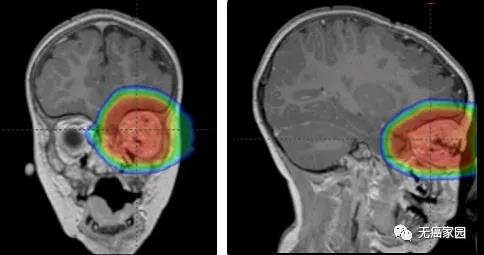

恶性脑肿瘤,包括胶质母细胞瘤、髓母细胞瘤等,通常都较为难治,是目前仍久攻不下的肿瘤类型,也是医学最热门的研究领域之一。而且众多专家的研究也表明,免疫疗法将有可能改...